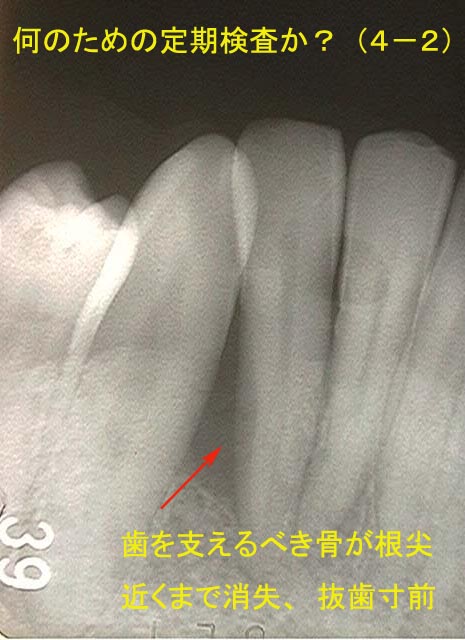

2―4.定期検査の実態

さて、以下に示す症例は中高年の方が定期検査を受け続けて安心されていた結果です。これら近年、FDCに転医された方に例外なくみられる症例です。

ブラッシングで歯周病は治ると指導され、動く歯を指で支えながらブラッシングを行ない定期的に受診。しかし、うがいの水もすごくしみ、歯の動揺のため咀嚼困難となりFDCを受診。

しかし、このような熱心な努力にもかかわらず現実には歯頸部から膿は漏出。

CT撮影を含めた総合診断の結果、治療方針は上顎5歯の抜歯。

簡便で低廉な検査ですから、このような結果もやむえないでしょうが、歯の弱い方には不幸な結果となっています。専門職として、またかかりつけ医ですから患者さんの信頼をうけている以上、もう少しなんとかならなかったのだろうかと思います。

3.平面レントゲンは診断に限界あり

通常の平面レントゲンの画像情報では歯槽骨の病的破壊が立体的にとらえることは困難です。ガンなどの悪性腫瘍はもちろん、歯周病や根先性歯周組織炎(歯根の先にできる病気)あるいは親知らずなど 歯槽骨に病状が及ぶ場合、CT撮影により信頼性の高い診断をくだすことができます。中高年の歯周病にはCT撮影を行っておけば、思わぬ多数の抜歯を宣告され慌てることはないでしょう。